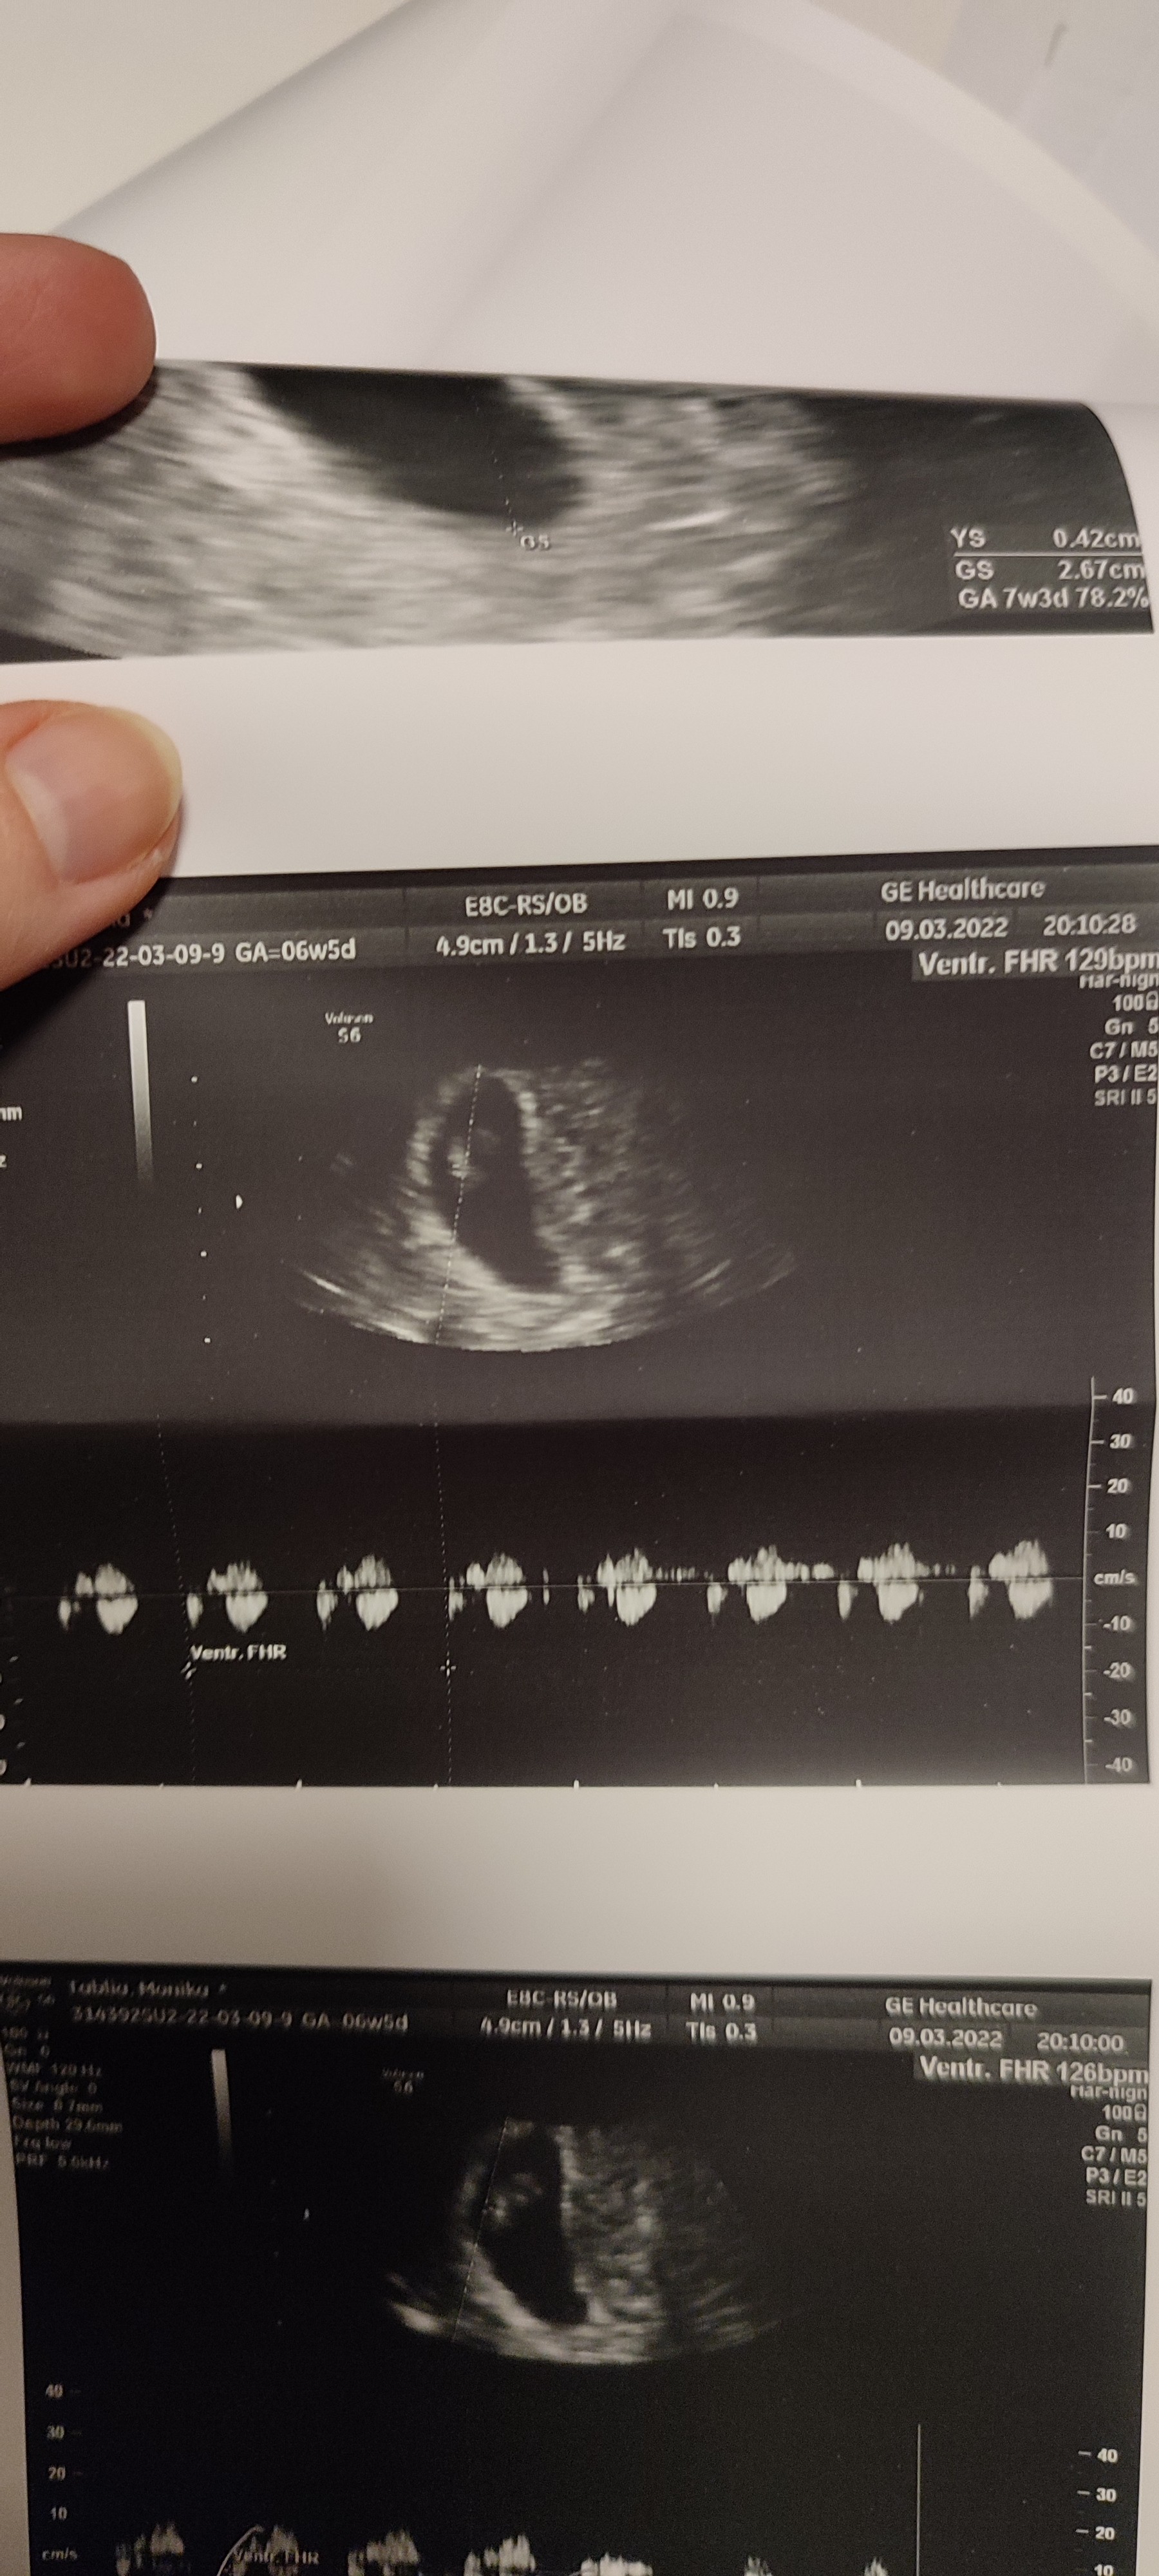

Oto moja fasolina 💕💕💕jednak niepotrzebnie się tak bałam, wszystko jest pięknie i co najważniejsze jest akcja serduszka 127 uderzeń na minutę. To bijące serduszko zrobiło na mnie ogromne wrażenie, jest to niesamowite:)

Załączniki

• IMG_20220309_203615.jpg

IMG_20220309_203615.jpg

1,1 MB · Wyświetleń: 110

• IMG_20220309_203527.jpg

IMG_20220309_203527.jpg

1,1 MB · Wyświetleń: 92